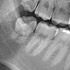

Nacholgend ein paar phänomenale Bilder & Werte,

die nicht nur einem Fachmann die Sprache verschlagen:

Aufnahmeparameter: Ceph LA; 82 kV; 10 mA; 8.0 s; 0.8 mm CU + 6.0 mm AL

gemessene Dosis: 2.99 µGy